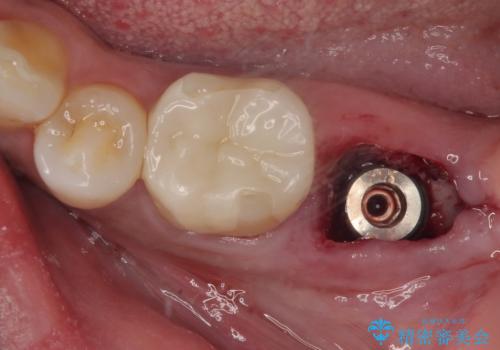

抜歯と同時にインプラントを埋入し、さらにその日のうちに仮歯を装着することで、見た目と機能を即日に回復しています。

従来のインプラント治療では、抜歯からインプラント埋入まで数か月の待機期間が必要でしたが、抜歯即時インプラントでは1回の外科処置で治療が完了するため、

・治療期間の短縮

・外科的侵襲(手術回数)の軽減

・患者さんの心理的・身体的負担の軽減

が可能です。